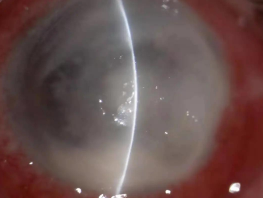

真菌性角膜炎是一種由致病真菌引起的、致盲率極高的感染性角膜病。常見的致病菌為曲霉菌,其次為鐮刀菌、白色念珠菌、頭芽胞菌及鏈絲菌等。可出現(xiàn)免疫環(huán)、衛(wèi)星灶、偽足、菌絲苔被、前方積膿及內(nèi)皮斑。